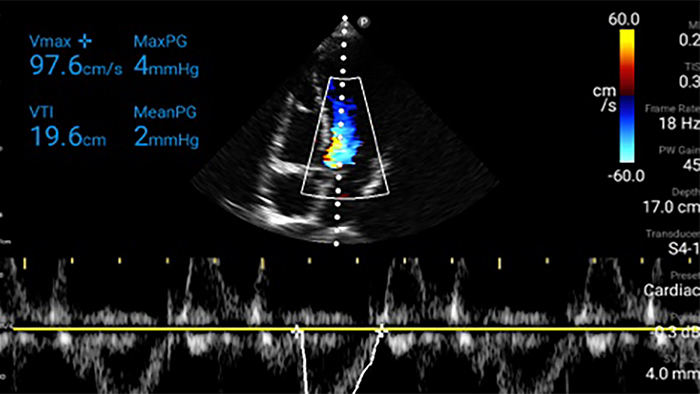

Exceptional ultrasound imaging

Lumify handheld ultrasound offers images that enhance diagnostic confidence.

See more when it counts

Lumify can help you make real-time decisions with more confidence, from assessment to recovery. Reveal the subtle details of an image, uncover enriched tissue definition with multiple angles and much more.